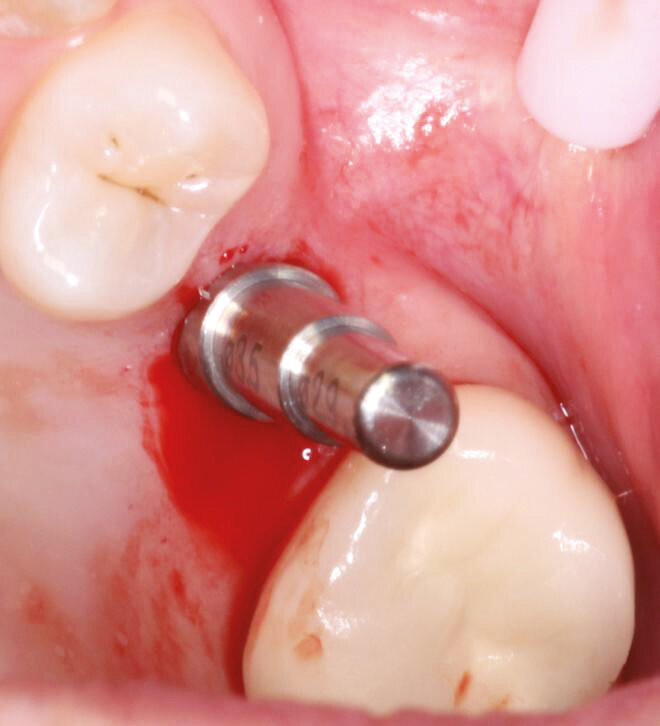

Fig.8: Optimal inter implant distance with the Axiom placement guide.

A 43-year-old female presents with missing premolar and molar upper right side (#15,16) and missing premolar upper left (#25). These teeth have been missing for 15+ years. A flapless approach was selected to minimize trauma and to facilitate quick healing. The Axiom Concept was utilized to create an emergence profile that would be difficult to detect from the natural dentition.